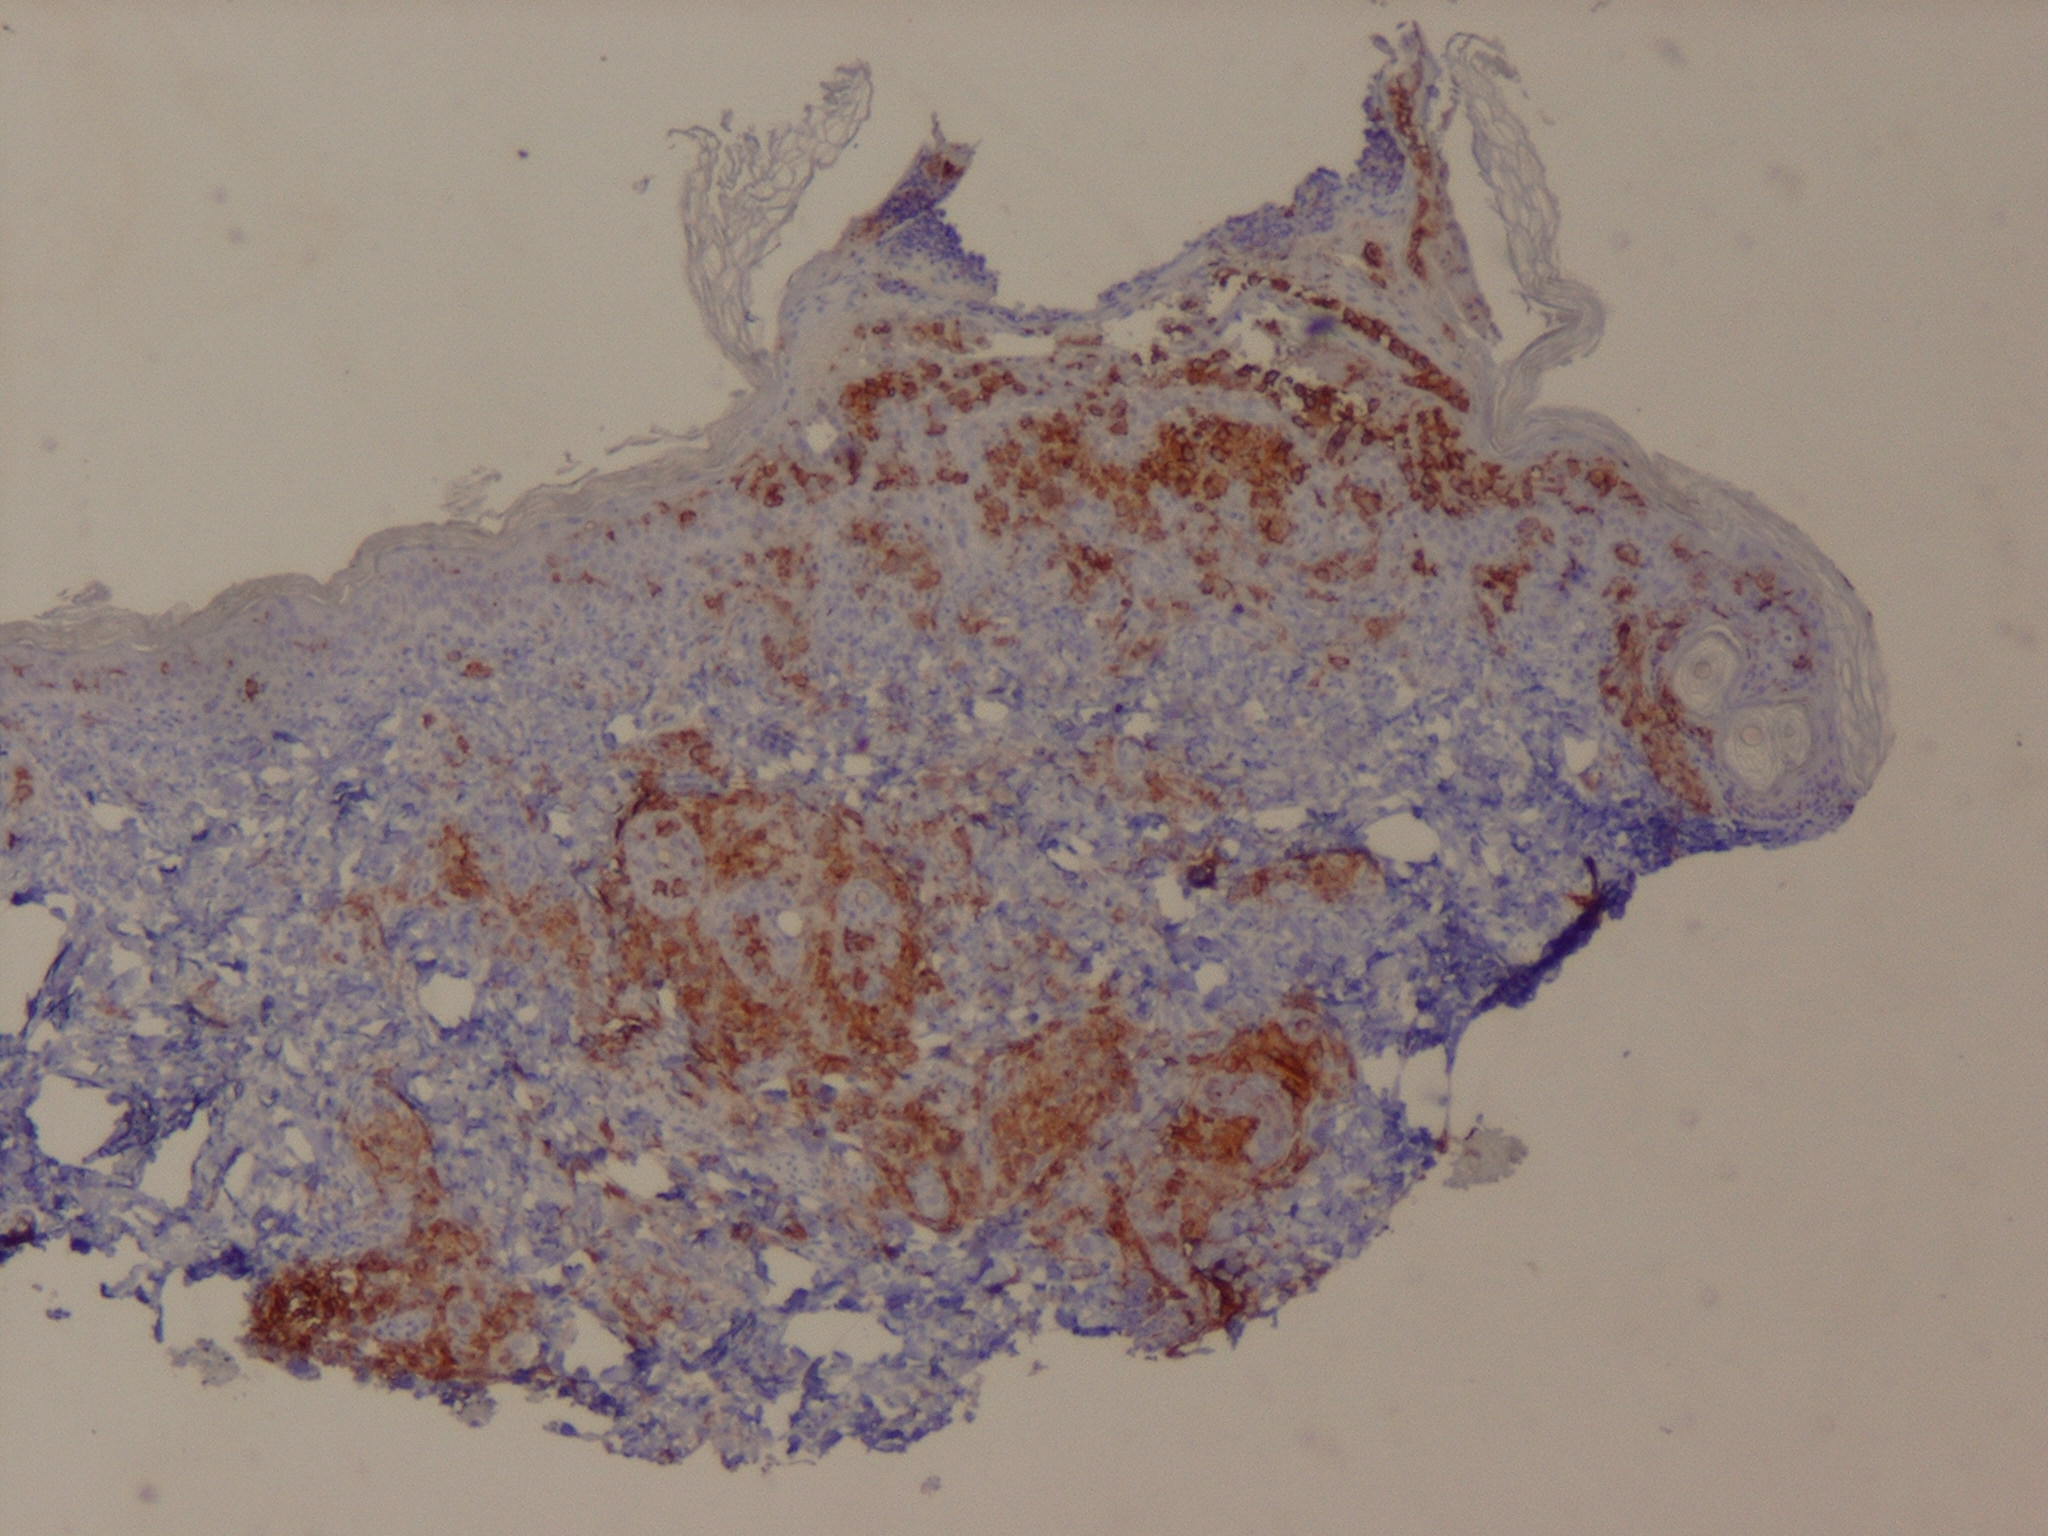

Langerhans cell histiocytosis = كثرة الخلايا الناسجة لانغرهانس